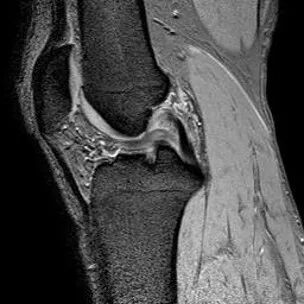

半月板桶柄状撕裂

1、多为纵形撕裂的特殊形式,有时来源于垂直(纵行)和水平撕裂2、多见于严重外伤的年轻患者3、内侧半月板发生率是外侧半月板的3倍

桶柄状撕裂MRI表现

1、宽度减小,在通过半月板体部的冠状面上蝶形消失,同时可见内移的半月板位于髁间窝、交叉韧带旁2、矢状面示残余的前角或后角变小或截断3、半月板前(后)角增宽或双半月板前(后)角征4、双前交叉韧带或双后交叉韧带征

桶柄状撕裂:宽度减小,在通过半月板体部的冠状面上蝶形消失,同时可见内移的半月板位于髁间窝、交叉韧带旁

桶柄状撕裂:半月板后角增宽